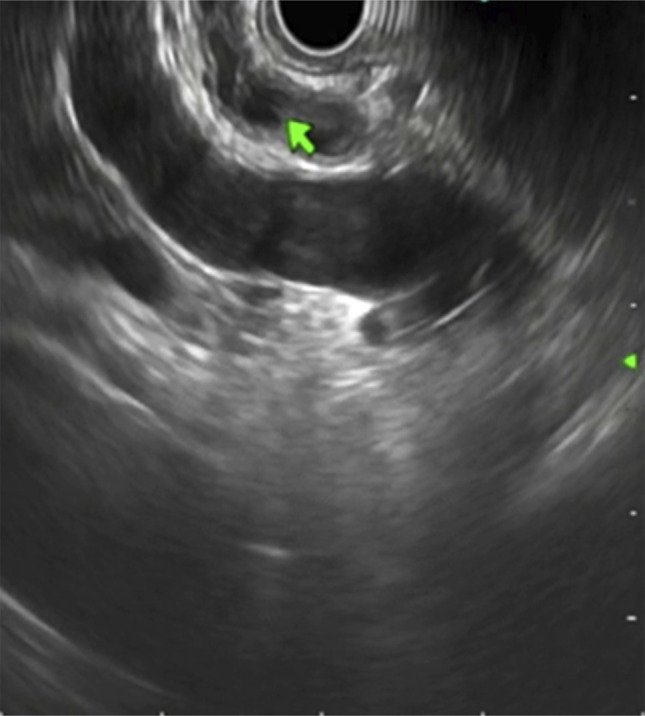

This is the first reported case demonstrating endoscopic ultrasound (EUS) findings in type Va duplication. The malformation of the congenital extrahepatic bile duct is classified as type Va and is rarely observed. To date, not more than 30 cases have been reported in Western literature. For the medical literature, a 50-year-old man with a type Va extrahepatic bile duct obstruction is examined. He presented with abdominal pain and jaundice, and imaging showed biliary dilatation and cholelithiasis. During the EUS procedure, an endoscopic examination revealed the presence of a duplicated common bile duct with a septum. Endoscopic retrograde cholangiopancreatography of the biliary tract also showed the same anomaly, with the presence of obstructive biliary sludge. The case highlights the need to consider EUS as a potent alternative diagnostic method. It is important to detect these anomalies immediately to reduce the chances of endoscopic/surgical complications.

Abstract Image